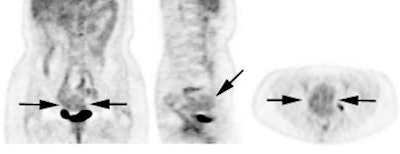

Genitourinary activity: The image below demonstrates activity within the collecting system of a transplanted kidney (black arrows). This should not be mistaken for an abnormality. |

|